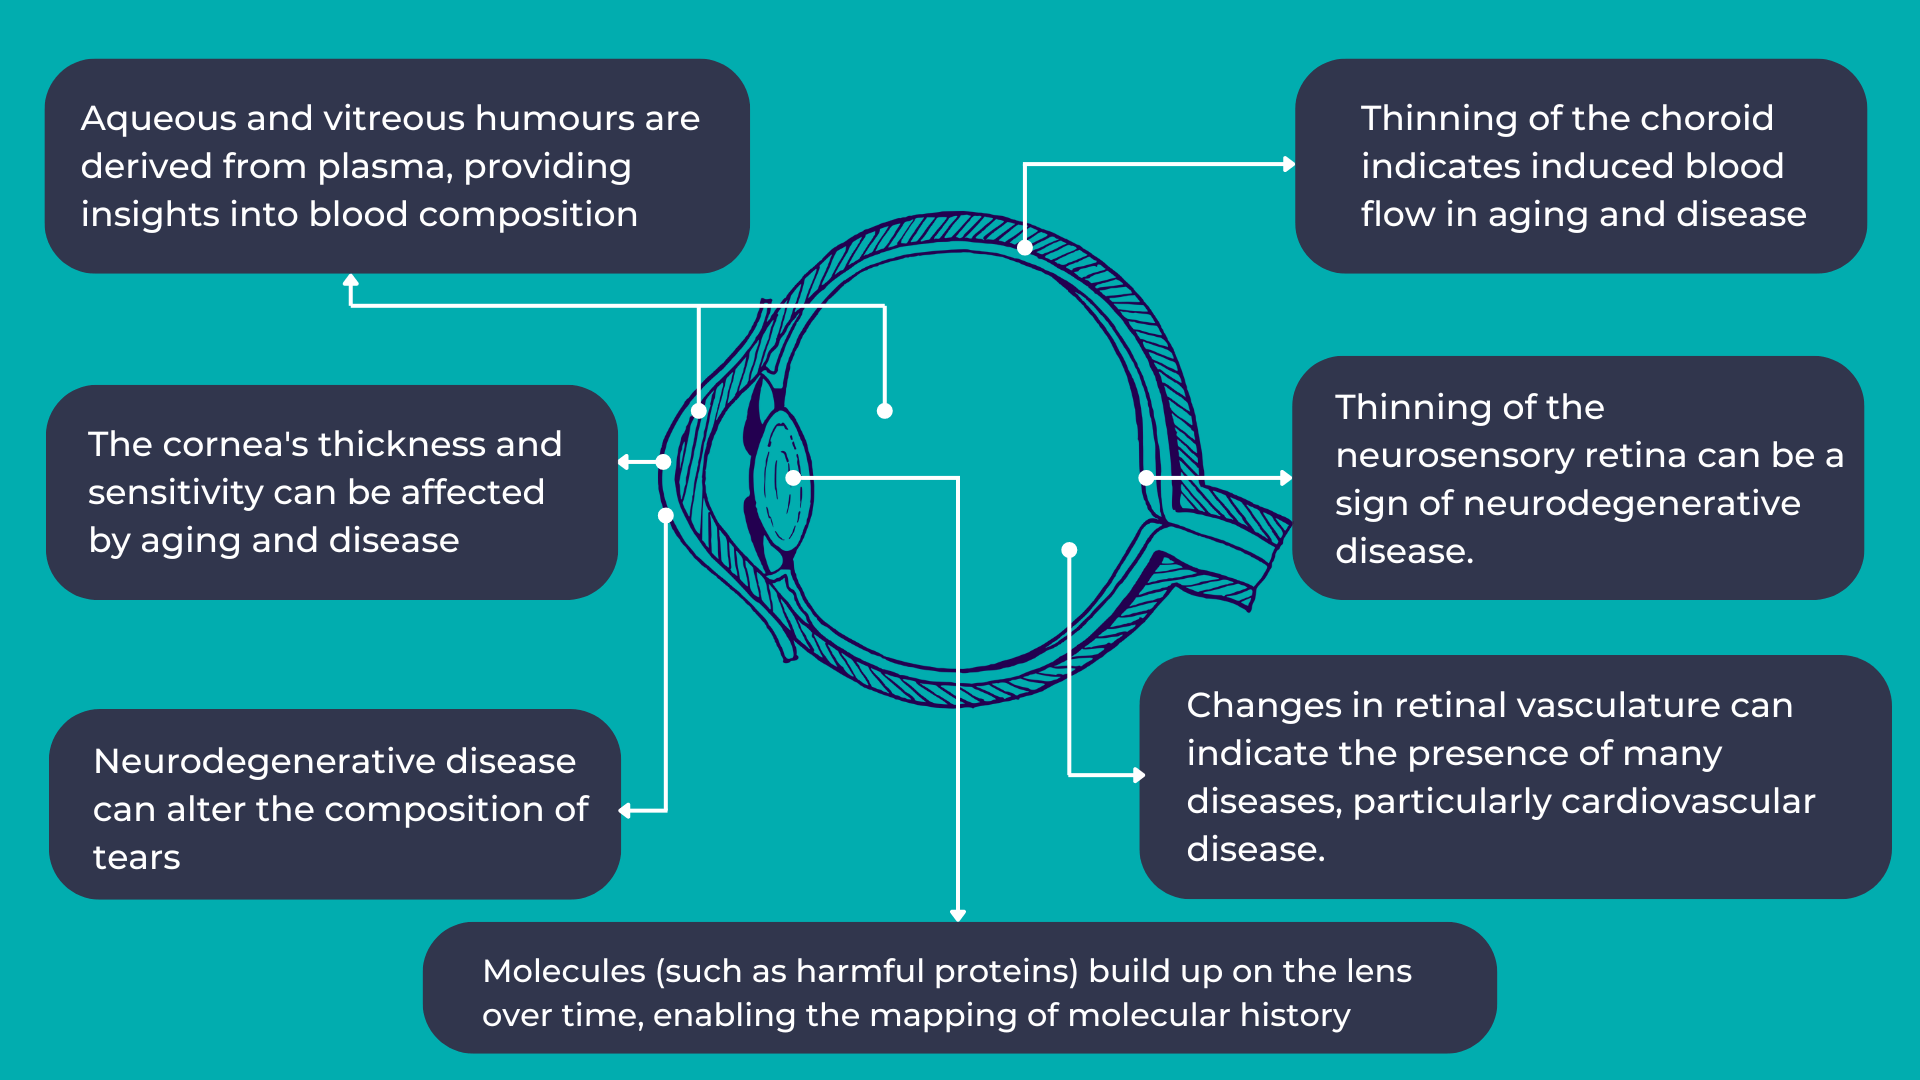

For decades, researchers have sought to measure retinal changes to identify ocular biomarkers for systemic diseases, a field now known as oculomics.

As mentioned earlier, the eye provides a unique opportunity for direct, in vivo, and often non-invasive visualization of the neurosensory and microvascular systems:

- The eye shares a common embryological origin with the brain, and the neurosensory retina and optic nerve are considered extensions of the brain, allowing direct observation of the nervous system.

- Due to the length and continuity of the visual pathway, along with trans-synaptic degeneration mechanisms, damage to the central nervous system often manifests as changes in the inner retina.

- The blood-retina barrier, similar to the blood-brain barrier, selectively allows the transport of essential substances to these metabolically active structures.

- The aqueous and vitreous humors are plasma-derived and transport lipid-soluble substances through diffusion and water-soluble substances through ultrafiltration.

- The lens, which grows continuously throughout life, accumulates molecules over time, providing a potential map of an individual’s molecular history.

The link between the eye and overall human health is not new. However, with the increasing availability and complexity of large, multimodal ocular image datasets, artificial intelligence-based ocular image analysis shows great promise as a noninvasive tool for predicting various systemic diseases. This is achieved by evaluating risk factors, retinal features, and biomarkers. Thanks to the massive datasets generated through recent ophthalmic imaging, which are now being used for deep learning and AI training, oculomics is starting to yield more precise answers. For example, the NHS alone has been conducting eye tests for over 60 years, resulting in databases containing millions of images, complete with patient records and long-term health outcomes. These datasets have been fed into AI algorithms, leading to models that can already predict cardiovascular risk factors with accuracy comparable to the current state-of-the-art methods.